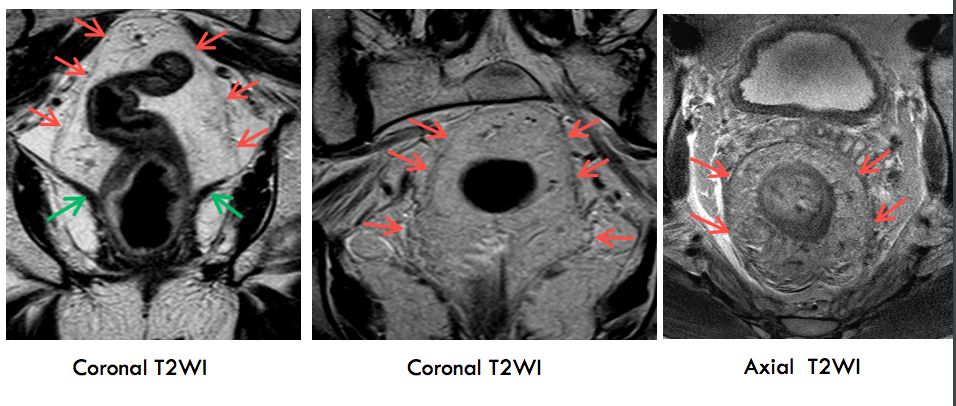

Hình 4. Khối ung thư trực tràng xâm lấn mỡ mạc treo trực tràng

Hình 5. Khối ung thư trực tràng giai đoạn T3 MRF-